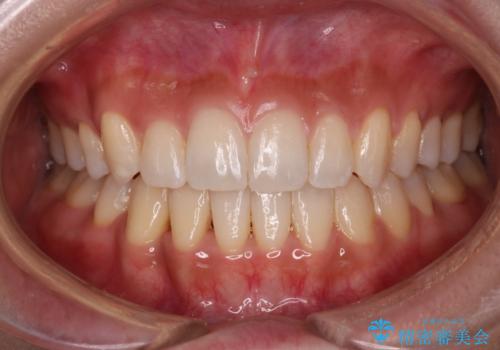

[マウスピース矯正] 海外留学中でも可能な矯正治療

担当医 大元洋佑

![[マウスピース矯正] 海外留学中でも可能な矯正治療の症例 治療後](https://seimitsushinbi.jp/wp/wp-content/uploads/2025/01/IMG_0074-500x350.jpg?v=1737343049)